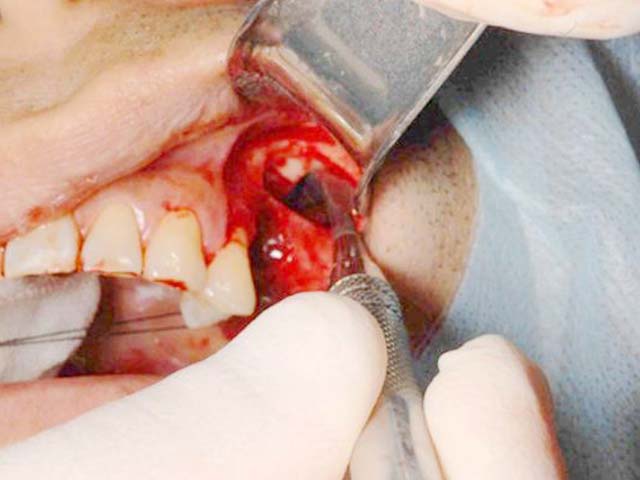

鼻竇增高術(側窗) 首頁 案例分享 人工植牙 鼻竇增高術(側窗) 鼻竇增高術(側窗) 製作多年的牙橋,牙根斷裂,發炎 鼻竇增高術 側面開窗 抬高鼻竇 鼻竇增高術 置入骨粉 覆蓋再生膜,保護骨粉 術後追蹤,傷口良好 裝戴正式假牙 完成 8年追蹤 左上牙根斷裂 植牙重建 九年追蹤